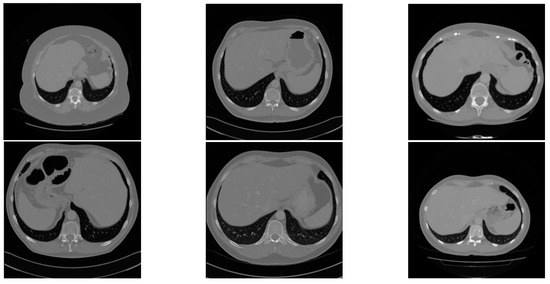

4.2. Data Preprocessing and Augmentation